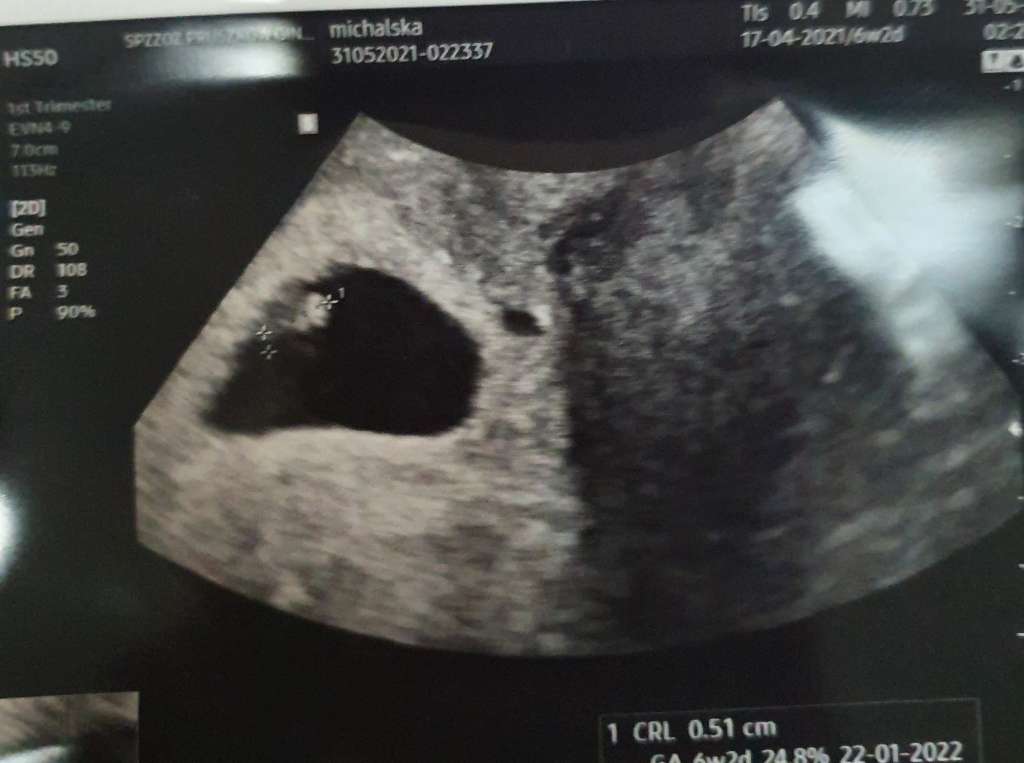

Cześć jestem Kropek mam 6tc+3 i moje serduszko juz bije ❤

Załączniki

• e089064a-d45c-4b22-b817-6b8a4e1d15a4.jpg

e089064a-d45c-4b22-b817-6b8a4e1d15a4.jpg

44,3 KB · Wyświetleń: 130